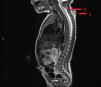

Al día siguiente se objetiva engrosamiento de la lesión con contenido serohemático que aumenta de tamaño con el aumento de la presión intraabdominal (fig. 2). Se realiza una ecografía cervical, que muestra un trayecto hipoecogénico que alcanza un área de pequeña ausencia de fusión de láminas posteriores. Se realiza una resonancia magnética, en la cual se visualiza un trayecto ascendente que alcanza el saco tecal, ligeramente dilatado a nivel de C4-C5, con médula levemente traccionada hacia el mismo con inclusión de las cubiertas meníngeas (fig. 3). A los 4 días de vida se realiza disección y cierre del defecto. La anatomía patológica describe tejido glioneuronal en dermis media-profunda con positividad para S100 y proteína glial fibrilar (GFAP), además de un tracto fibroso incompleto con celularidad positiva para GFAP.